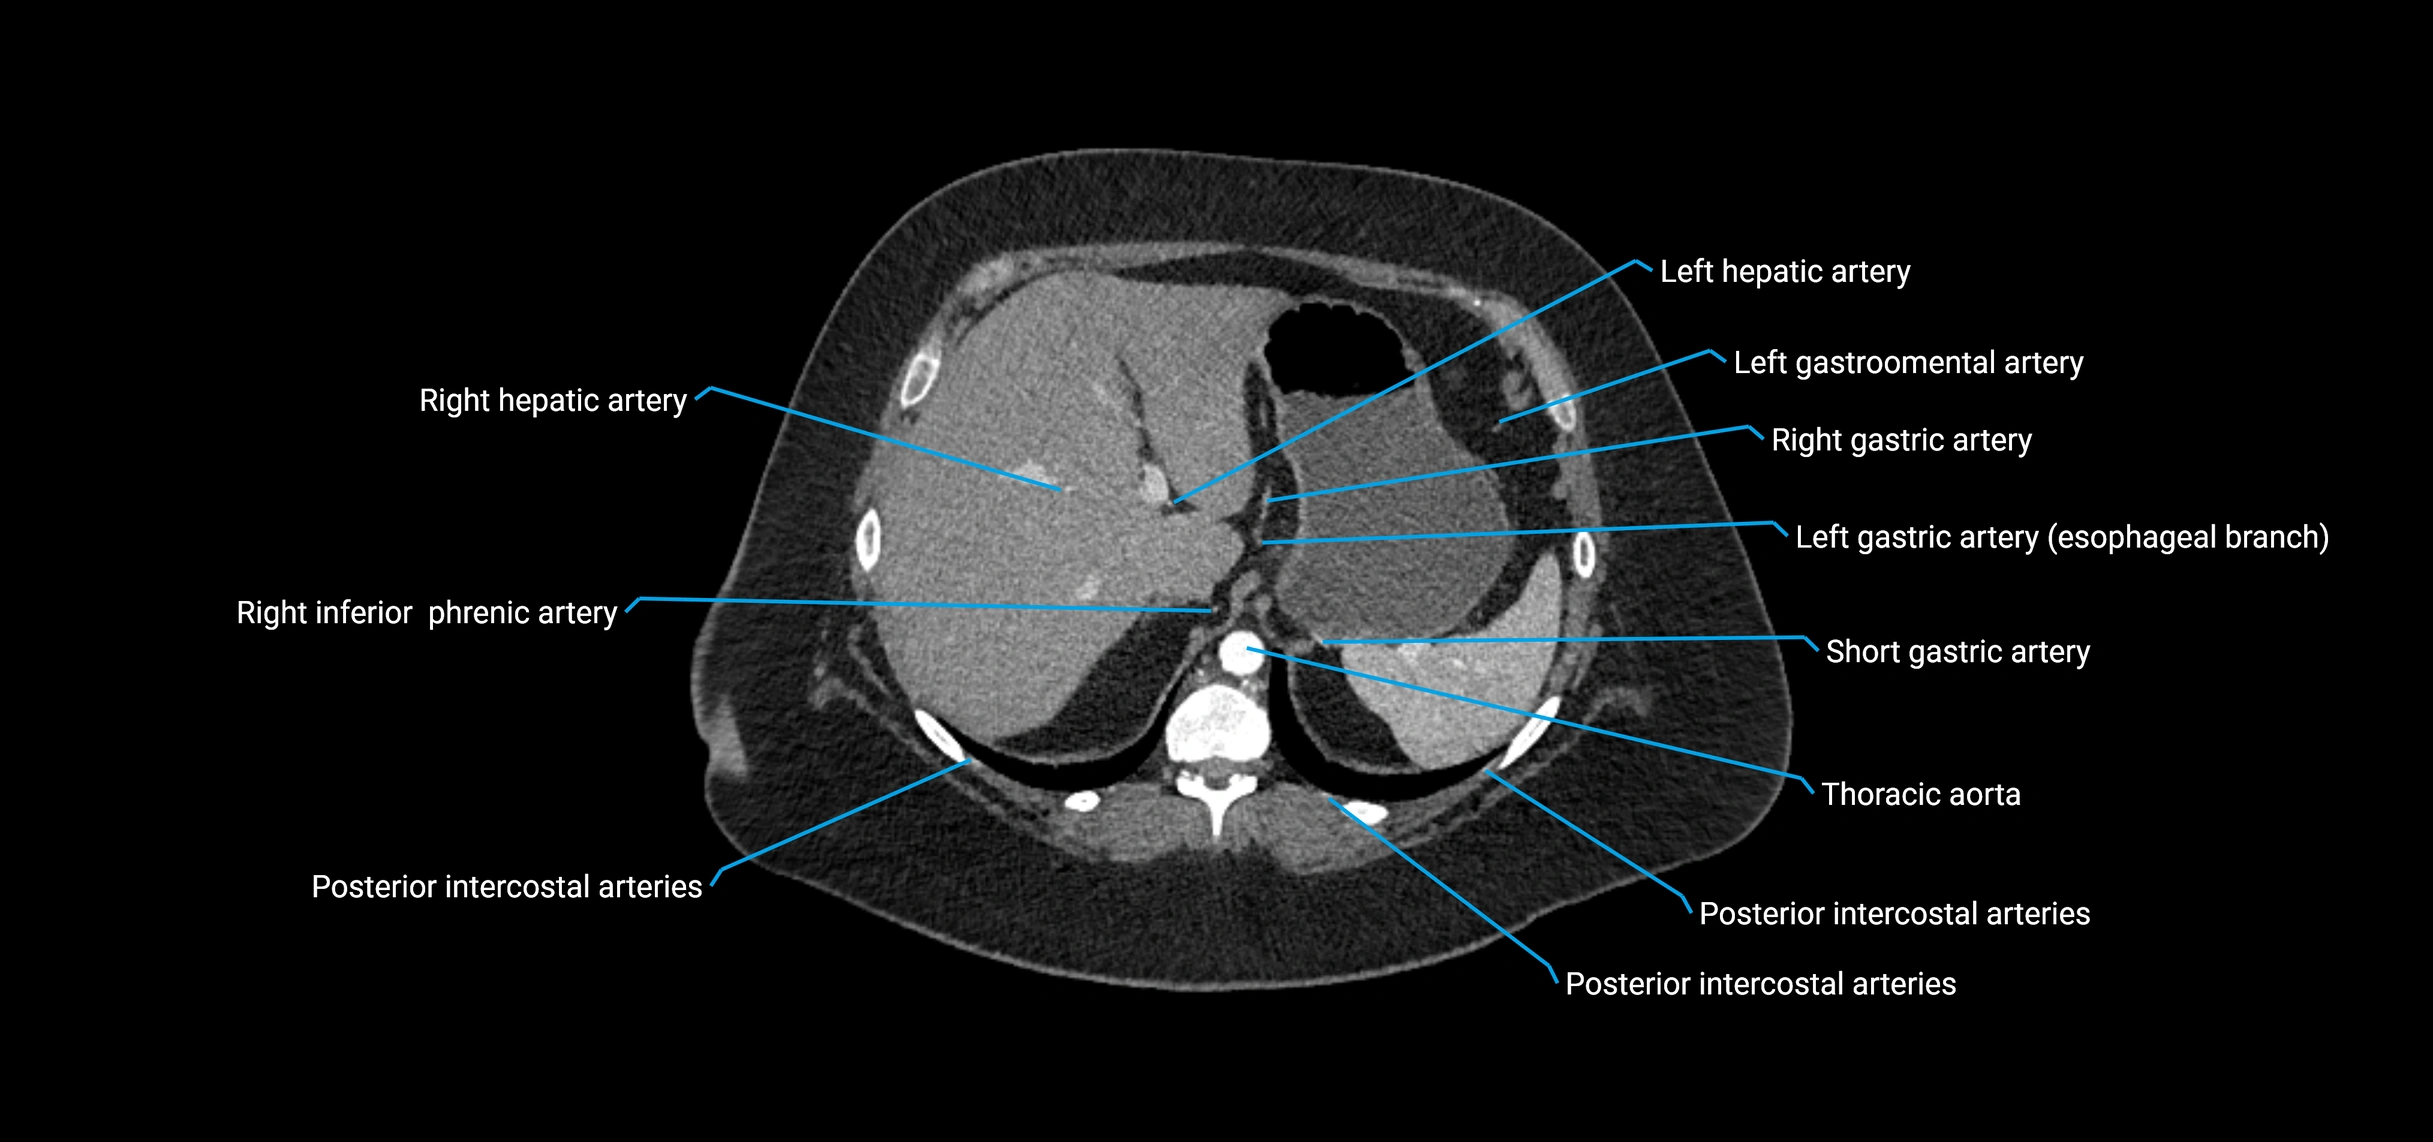

CT images

image

Contrast-enhanced CT (CTA):

• Gold standard for abdominal aortic imaging

• Provides excellent detail of lumen, wall, aneurysm, thrombus, and branch vessels

• Multiplanar and 3D reconstructions help in aneurysm measurement, stent graft planning, and dissection evaluation